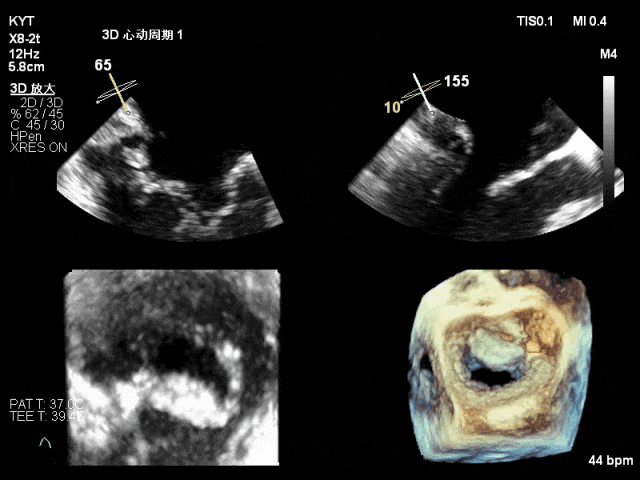

术前超声评估结果:

二尖瓣PC区收缩期脱向左房侧,其上可见飘带样回声。二尖瓣口左房侧见大量反流信号,主要呈偏心性并沿前叶走行达房顶并折返。

TEE 3D示二尖瓣内交界区脱垂及断裂腱索